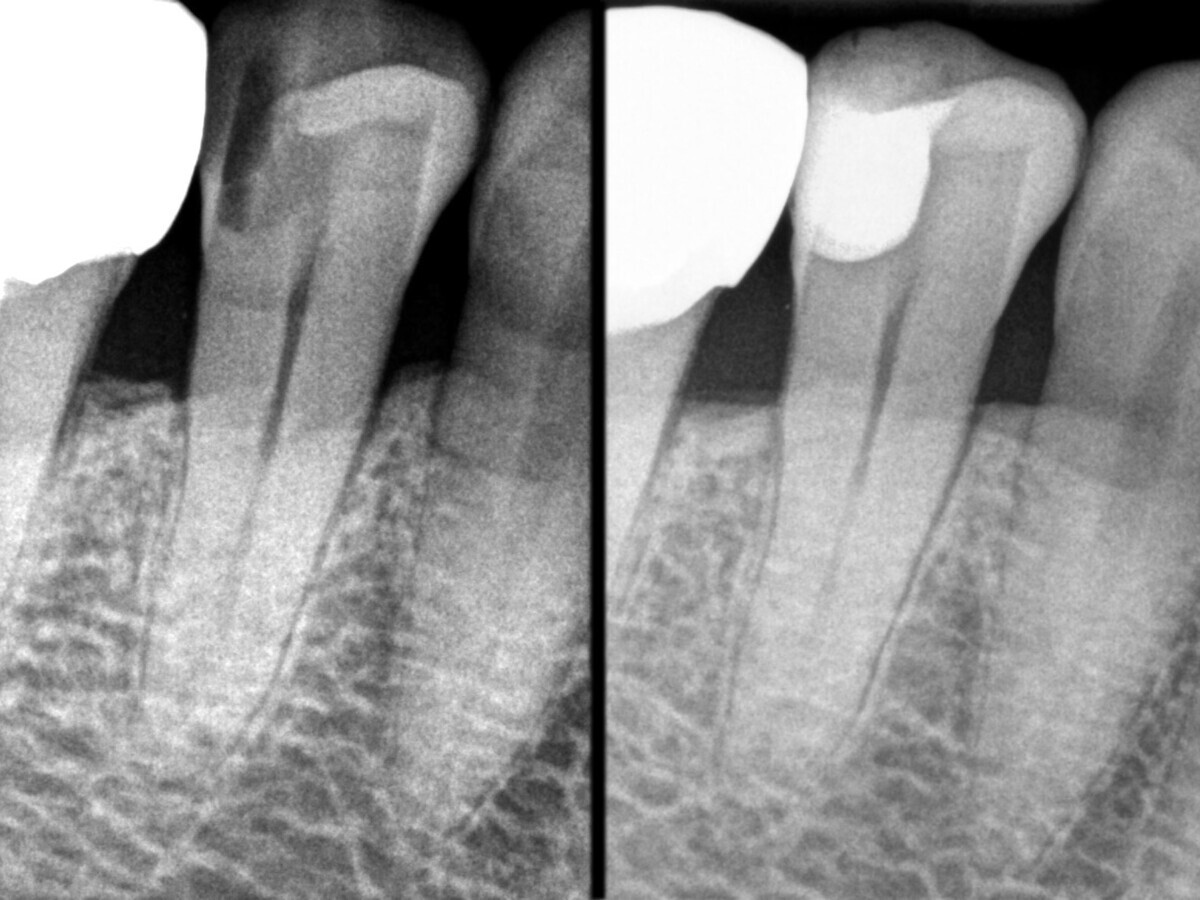

La comparación de las radiografías pre y postoperatorias demuestra la calidad del tratamiento (Figura 23).

Figura 23. Radiografías pre y postoperatorias.

Gracias a las excelentes propiedades de aplicación del composite termoviscoso, la restauración no presenta burbujas de aire. Además, existe uniformidad entre los dos composites utilizados en términos de visibilidad de rayos X, y, en general, la restauración presenta un aspecto homogéneo, sin transiciones visibles entre el composite de base fluida y el composite de relleno en bloque. La radiografía preoperatoria no pudo mostrar la extensión completa de la lesión. Solo durante el tratamiento se hizo evidente la necesidad de una preparación exhaustiva para eliminar por completo la estructura dental afectada. Para preservar la vitalidad de la pulpa, se realizó una desensibilización antes de la restauración con composite.